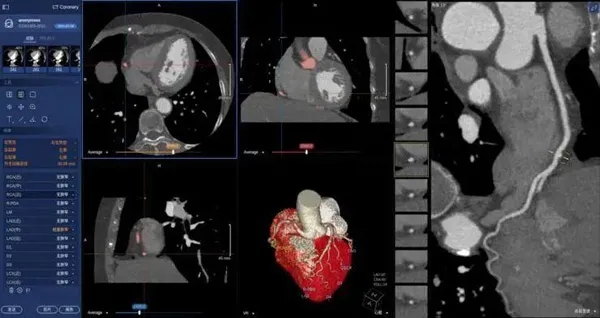

在醫(yī)學(xué)領(lǐng)域,機(jī)器視覺主要用于醫(yī)學(xué)輔助診斷。首先采集核磁共振、超聲波、激光、X射線、γ射線等對人體檢查記錄的圖像,再利用數(shù)字圖像處理技術(shù)、信息融合技術(shù)對這些醫(yī)學(xué)圖像進(jìn)行分析、描述和識別,最后得出相關(guān)信息,對輔助醫(yī)生診斷人體病源大小、形狀和異常,并進(jìn)行有效治療發(fā)揮了重要的作用。不同醫(yī)學(xué)影像設(shè)備得到的是不同特性的生物組織圖像,如X射線反映的是骨骼組織,核磁共振影像反映的是有機(jī)組織圖像,而醫(yī)生往往需要考慮骨骼有機(jī)組織的關(guān)系,因而需要利用數(shù)字圖像處理技術(shù)將兩種圖像適當(dāng)?shù)丿B加起來,以便于醫(yī)學(xué)分析。